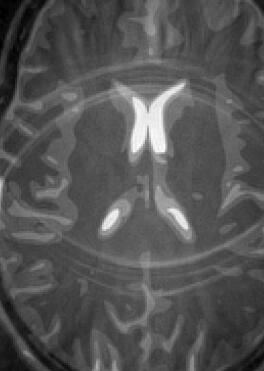

Fig. 14 exhibits the reconstruction results with the spiral trajectory with for . The reconstructed images are displayed alongside profile plots of row . The same is also presented in Figures 13 for .

When sampling on a spiral trajectory, SPURS further demonstrates its superior performance over the other methods. For values high enough, SPURS, NUFFT and rBURS with achieve very good results, but the performance curve for each method levels off for different values of (Figures 9, 10, 11 and 12). Iterative SPURS levels off for values as low as , requiring about iterations to converge to its best result. For these low values, significant artifacts appear in the reconstructed image produced by all methods excluding SPURS as presented in Fig. 13 for and Fig. 14 for . The performance curve of the NUFFT method and of a single iteration of SPURS level off at around . For and higher, a single iteration of SPURS produces marginally better results than those produced by NUFFT, which requires about iterations to converge. Among the other non-iterative methods, both rBURS with and convolutional gridding perform similarly well for , however the results are still inferior to those of a single iteration of SPURS, all of which have similar computational complexity.